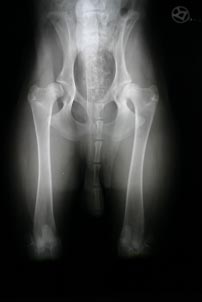

Röntgentermin bei unserem Tierarzt. Was für ein Schock:

Schwere HD mit Athrose auf beiden Seiten und eine defekte Patellarsehne

rechts.

"Takahara (Akita Inu, m) wurde am 19.08.2004 im Alter von 8

Monaten im Vierbeiner Reha-Zentrum vorgestellt. Vorberichtlich war aufgrund

unrunden Laufens eine Röntgenaufnahme der Hüften durchgeführt

worden, die eine beidseitig vorliegende Hüftgelenkdysplasie mit

zarten koxathrotischen Anzeichen dokumentierte. Grund der Konsultation